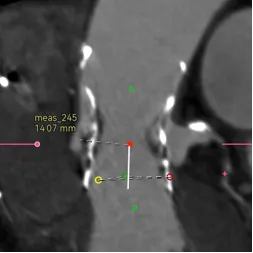

在这个病例中,我们能够看到升主对于瓣膜的推挤还是很大的,我们既往对于升主的长度有些人会用来评估同轴性,但是很多喜欢量中间来跟支架长度作对比,但实际上要量大弯侧边缘的到转弯地带的长度。

另外还可以看到二叶瓣的瓣膜植入进去,实际上瓣环那边是空的,虚拟瓣环没有任何锚定和封堵作用,实际上的锚定和封堵都是靠瓣上空间。二叶瓣的瓣膜选择需要抛弃依赖瓣环这个习惯。要综合考虑瓣上限制,过大oversize会导致框架扩张不充分(内折或者过度压缩)、瓣叶卷曲等影响血流动力学。笔者一直很反对过度的oversize。